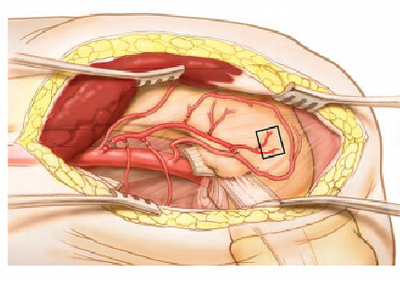

При васкуларизираните костни трансплантати биологичните особености са коренно различни. Всяка една жива тъкан в човешкия организъм разполага с капилярна мрежа, която в някои тъкани е по-богата, в други - по-бедна, но винаги съществува. На схемата долу е показано едно типично васкуларизирано ламбо - то представлява сегмент от тъкани в различна комбинация, но най-често съдържа кожа, мускул и костна тъкан. При различните видове дефекти може да се използват различни комбинации - в зависимост от типа на тъканите, които подлежат на реконструкция. Очевидно е че при излишък от кожа няма необходимост от вземане на кожен участък от реципиентната ложа, което силно намалява вероятността от увреждане там; при резекция на карцином на бузата пък с последваща едномоментна реконструкция няма необходимост ламбото да съдържа и костна тъкан.

Така наречените кожни перфорантни съдове са от ключово значение за оцеляването на васкуларизирания трансплантат. На горната схема те са означени с Р1 и Р2 - перфоратор 1 и 2. Тези съдове захранват кожния участък и осигуряват едно адекватно кръвоснабдяване, устойчиво за продължителен период от време. Постепенно процесите на реваскуларизация напредват и перфорантните съдове губят своето клинично значение - от съседните участъци в реципиентната ложа прорастват нови и нови капиляри, венули и артериоли и трансплантатът става все по-стабилен и витален. Тъй като в участъците, подложени на травматични промени (включително и ятрогенни), обмяната е силно ускорена, репаративните процеси всъщност са доста бързи. От голяма полза за това е хипербарната оксигенация.

Класическата триада на всяко микросъдово ламбо обхваща три компонента - артерия, вена и нерв. На горната схема те са означени съответно с латинските букви A, V и N. За да оцелее едно ламбо и за да се образува адекватно количество костен обем, е необходимо свързването на артерията и вената; при провал в микросъдовата анастомоза е по-опасно тромбозирането на артерията, но и венозният застой води до чести провали. Свързването на един нерв от ламбото към избран друг нерв в реципиентната ложа подобрява значително трофиката на трансплантата и дори осигурява неговата сенсибилизация - присадените тъкани стават чувствителни. Това обаче така или иначе ще се случи на по-късен етап, тъй като нервните влакна (особено сензитивните, в по-малка степен двигателните) имат свойството да прорастват в посока към всяка една присадена тъкан. Подобряването на изхранването на тъканите обаче определено представлява предимство - особено при премахване на неопластични процеси, които подлежат и на постоперативно лъчелечение. Поради това ако желае да бъде максимално прецизен и да помогне по възможно най-добрия начин на своя пациент, хирургът просто трябва да осъществи и невроанастомоза.